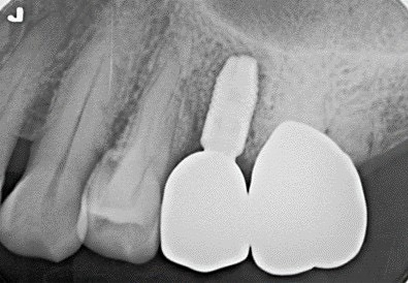

Before術前

After術後